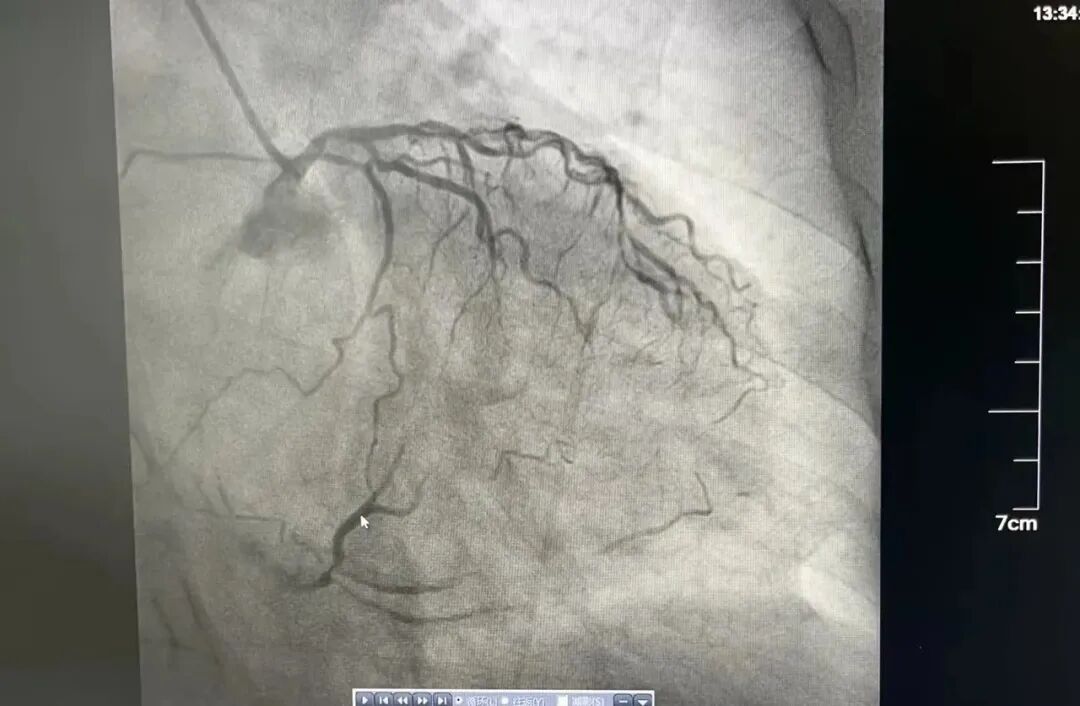

“让一让,病人要立即抢救”,一名老年女性患者正躺在推车上,向心内科导管室飞奔而去。患者持续胸痛,危重症急性心肌梗死,需要立即抢救。此时,心内科主任医师漆军华、主治医师张敦福已经在手术室等待。 漆军华了解到,患者有高血压及劳力性胸痛20多年,3天前起反复胸痛,此次因胸痛持续就诊,结合心电图判断,患者很可能冠脉病变复杂,遂立即向心内科主任陈立娟汇报病情,陈立娟主任指示立即行冠脉造影。 果不其然,冠脉造影结果显示严重三支病变,左主干疑似夹层,左前降支全程严重钙化纤细伴重度狭窄,左回旋支开口狭窄95%以上,可见左冠向右冠提供侧枝循环,右冠状动脉巨大,全程严重钙化,中段完全闭塞,且患者持续胸痛不缓解,血压偏低,基本可以判定患者病情危重,随时有生命危险。 陈立娟仔细查看造影影像后,判断立即行血运重建是拯救患者生命的唯一出路,溧水区人民医院导管室有抢救危重患者的利器——主动脉球囊反博(IABP),建议在主动脉球囊反博(IABP)支持下进行手术。 得到家属同意后,值班护士张燕萍、周红迅速启动IABP机器,配好抢救药品,陈立娟与漆军华穿上铅衣准备上台。看着严阵以待的心内科团队,家属对医院充满了信赖。 手术准备就绪,陈立娟和漆军华迅速穿刺股动脉,送入IABP球囊,两位护士熟练地连接好主动脉球囊反博仪并打开机器,此时患者胸痛有所减轻。左指引导管到位后,工作导丝通过前降支病变送至远端,但因患者冠脉钙化严重,即使最小的球囊也无法通过病变。 面对困境,陈立娟果断改变思路,患者右冠巨大,供血范围极大,如果能开通右冠,有极大的可能性保住患者生命线,幸运的是,在微导管后支撑下,工作导丝很快就通过了中段闭塞病变,随后在右冠植入支架,支架植入后,患者胸痛明显缓解,生命危险终于解除。手术很成功,患者术后转中大医院继续治疗,目前恢复良好,已经出院。